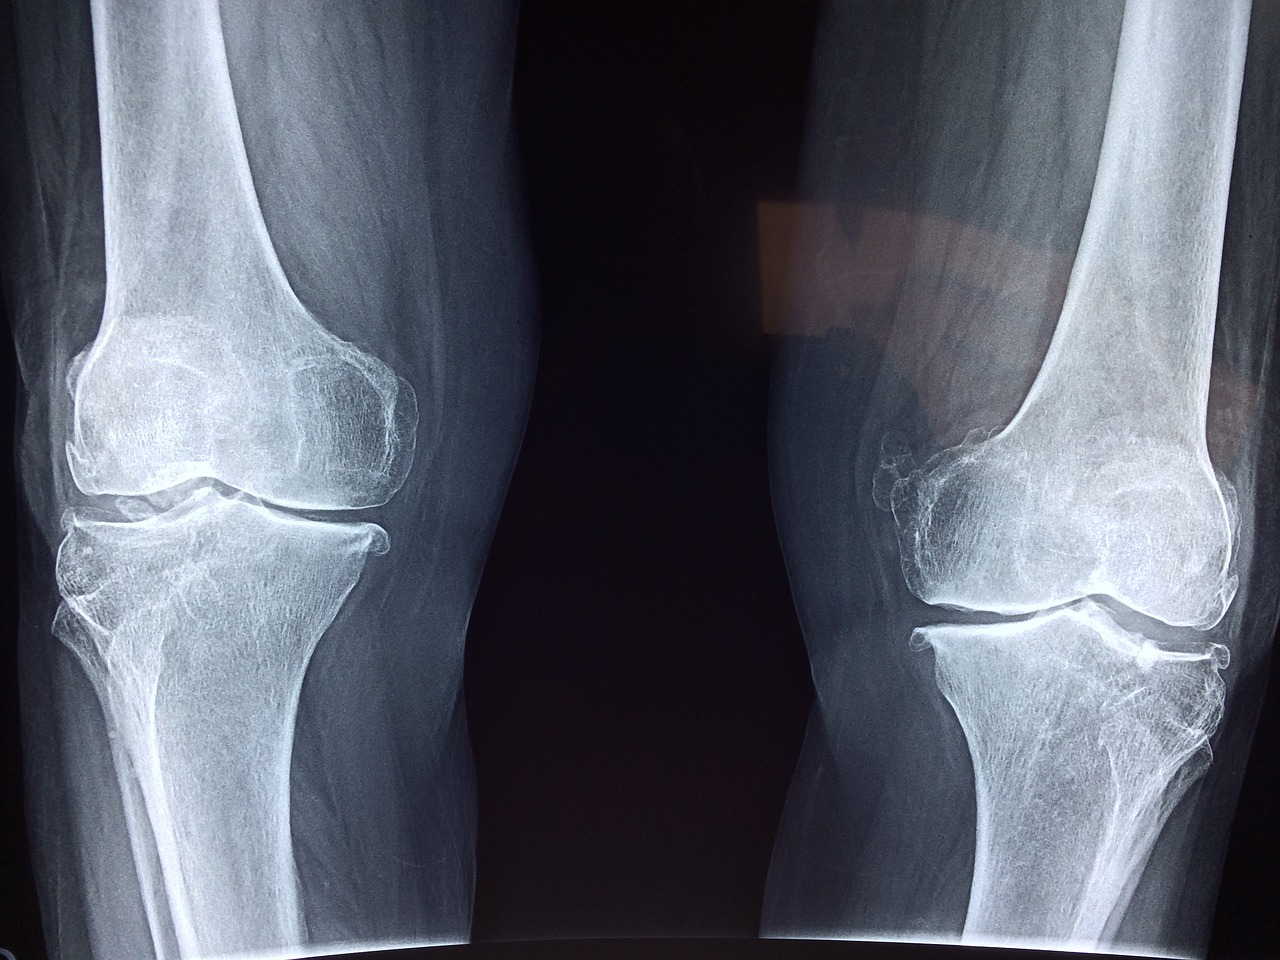

글루코사민은 연골 조직의 건강을 유지하는 데 도움을 줄 수 있습니다. 연골은 관절강 내부의 뼈를 보호하고 관절의 움직임을 부드럽게 만들어주는 역할을 합니다. 관절의 노화와 염증 등으로 인해 연골 조직이 파괴되면, 글루코사민은 손상된 연골을 재생하고 관절의 건강을 개선하는 데 도움을 줄 수 있습니다.

1. 슬관절염 관리: 일부 연구는 글루코사민이 슬관절염의 증상을 완화하는 데 도움이 될 수 있다고 주장하고 있습니다. 글루코사민은 연골 조직을 유지하고 재생하는 데 도움을 주며, 관절 통증과 염증을 감소시킬 수 있는 작용이 있을 수 있습니다. 그러나 이에 대한 연구 결과는 상충되므로 효과의 정도는 개인에 따라 다를 수 있습니다.

2. 연골 보호: 글루코사민은 연골 조직의 주요 구성 성분인 그리코사미노글리칸의 생성을 촉진하여 연골의 탄성과 내구성을 향상시킬 수 있습니다. 이는 연골 조직을 보호하고 파괴를 줄이는 데 도움이 될 수 있습니다.

4. 연골 재생: 몇 가지 연구에서는 글루코사민이 손상된 연골 조직을 재생하고 염증을 감소시키는 데 도움이 될 수 있다고 주장하고 있습니다. 그러나 이에 대한 연구는 아직 제한적이며, 더 많은 연구가 필요합니다.